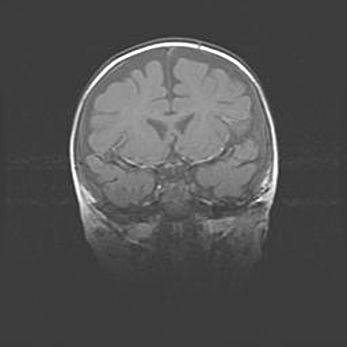

Открытая гидроцефалия.

Возраст: 6 месяцев 15 дней

Вес: 6200 г

Пол: женский

Окружность головы: 41 см

Срок гестации: 38 недель

Гидроцефалия головного мозга у новорожденных – это скопление избыточного количества цереброспинальной жидкости в головном мозге. Ее избыточное скопление в мозге приводит к патологическому расширению желудочков мозга (четырех полостей, расположенных в глубине белого вещества мозга, заполненных цереброспинальной жидкостью и связанных узкими проходами).

Открытый тип гидроцефалии (сообщающаяся) наблюдается тогда, когда нарушен механизм всасывания ликвора в системный кровоток. При этом типе причиной заболевания чаще всего является перенесенные ранее инфекции (например: менингит),  либо же наличие крови в субарахноидальном пространстве.